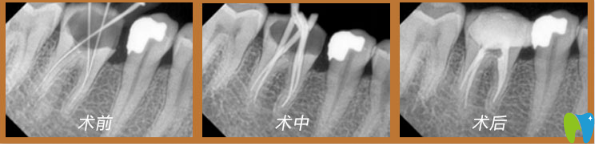

董克文院長(zhǎng)真人案例:

謝先生,33歲,癥狀:牙齒蛀蟲;解決方案:歐式無(wú)痛顯微根管治療。

術(shù)前口述:患上牙髓炎十分痛苦,特別是夜里,劇烈疼痛,吃止疼藥根本不管用,平日吃東西也不敢嚼,人都憔悴了。

術(shù)后感言:治療的時(shí)候醫(yī)生首先在牙齒上鉆一個(gè)洞(打過(guò)麻藥的情況),將炎性分泌物釋放出來(lái),效果立竿見(jiàn)影,馬上就感覺(jué)牙齒不疼了。牙疼是病,得治!